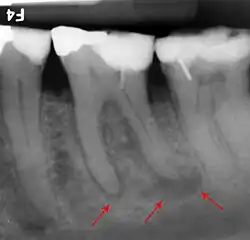

Zahnmedizin

In der Zahnmedizin ist die Ausprägung der Röntgenopazität ein fester Bestandteil der Diagnostik und Behandlungskontrolle. Im Vergleich zu einer 1 mm dicken Aluminiumschicht (100 %) ist Dentin 118 % und Schmelz 215 % röntgenopak. Zur Beurteilung der Dichtigkeit von Zahnfüllungen sollten diese eine Röntgenopazität von 200 % aufweisen. Glasionomerzemente besitzen eine Röntgenopazität von 200–250 %, Komposite von 250–350 %.[4] Aluminium-Silikatgläser weisen in der Regel keine genügende Radioopazität auf. Das Einfügen von geeigneten Elementen in das Aluminiumsilikatglas, beispielsweise in Form eines Austausches von Calcium in der Glaskomposition durch Barium oder Strontium, stellt diese her.[5] Die radiologische Darstellung kariöser Läsionen beruht auf der Visualisierung kariöser Läsionen über die Abnahme der Radioopazität der erkrankten Zahnhartsubstanzen, die durch den Verlust an Mineralien hervorgerufen wird.[6]